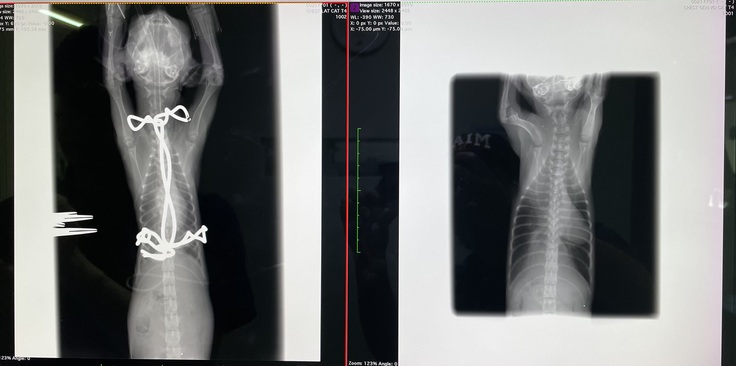

※写真 (左)after (右)before

思ってたより骨が変形していたそうで、肋骨の軟骨もすごい形をしていたそうです。歪んでいた心臓も術後はほぼ正常な位置に戻りました。

すごく骨が変形していた為、完全には綺麗な形にはならなかったみたいです。成長していくにつれて、少しずつコルセット(ギプス)を調整していき、様子を見ていく、とのことでした。

漏斗胸の胸骨矯正手術が無事に終わりました。